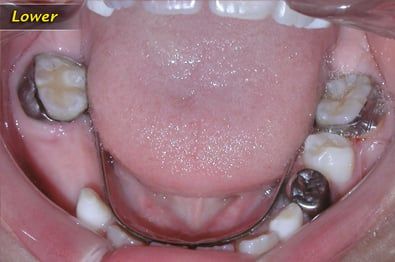

Lingual Arch

A lower lingual arch is a space maintainer for the lower teeth. It maintains the molars where they are and it does not move them. It keeps the molars from migrating forward and prevents them from blocking off space of teeth that develop later. Used when early loss of baby teeth or when lower teeth are slightly crowded.